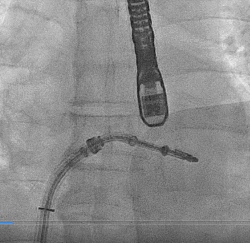

患者全麻以后,在经食道超声心动图和X射线引导下,经股静脉入路,将MitraClip瓣膜夹顺利送至二尖瓣前后叶交界中心处,成功捕捉二尖瓣前叶A2和后叶P2,经超声心动图反复确认瓣叶夹持牢固后,测定有效夹持长度10.4mm,评估反流量降至轻度,释放瓣膜夹,超声心动图评估瓣膜夹位置和功能良好,测定左房压降至26/12mmHg,再次评估反流量仍为轻度,手术顺利完成。

▲ MitraClip释放